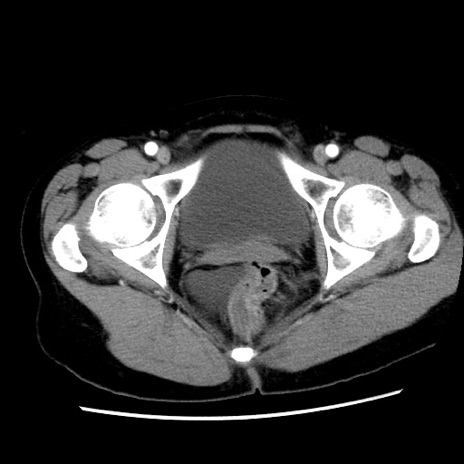

症例10(横断像)

【症例】 50歳代女性

【主訴】 腹痛

【現病歴】前日生レバーを食べた。今朝に排便あり。 昼前に突然発症の腹痛を生じ、当院救急外来を受診した。

【既往歴】 子宮筋腫にてで子宮全摘後

【身体所見】 意識清明、腹部:平坦、軟、下腹部やや左を中心に圧痛・反跳痛あり、筋性防御あり

【データ】WBC 7800、CRP 0.07